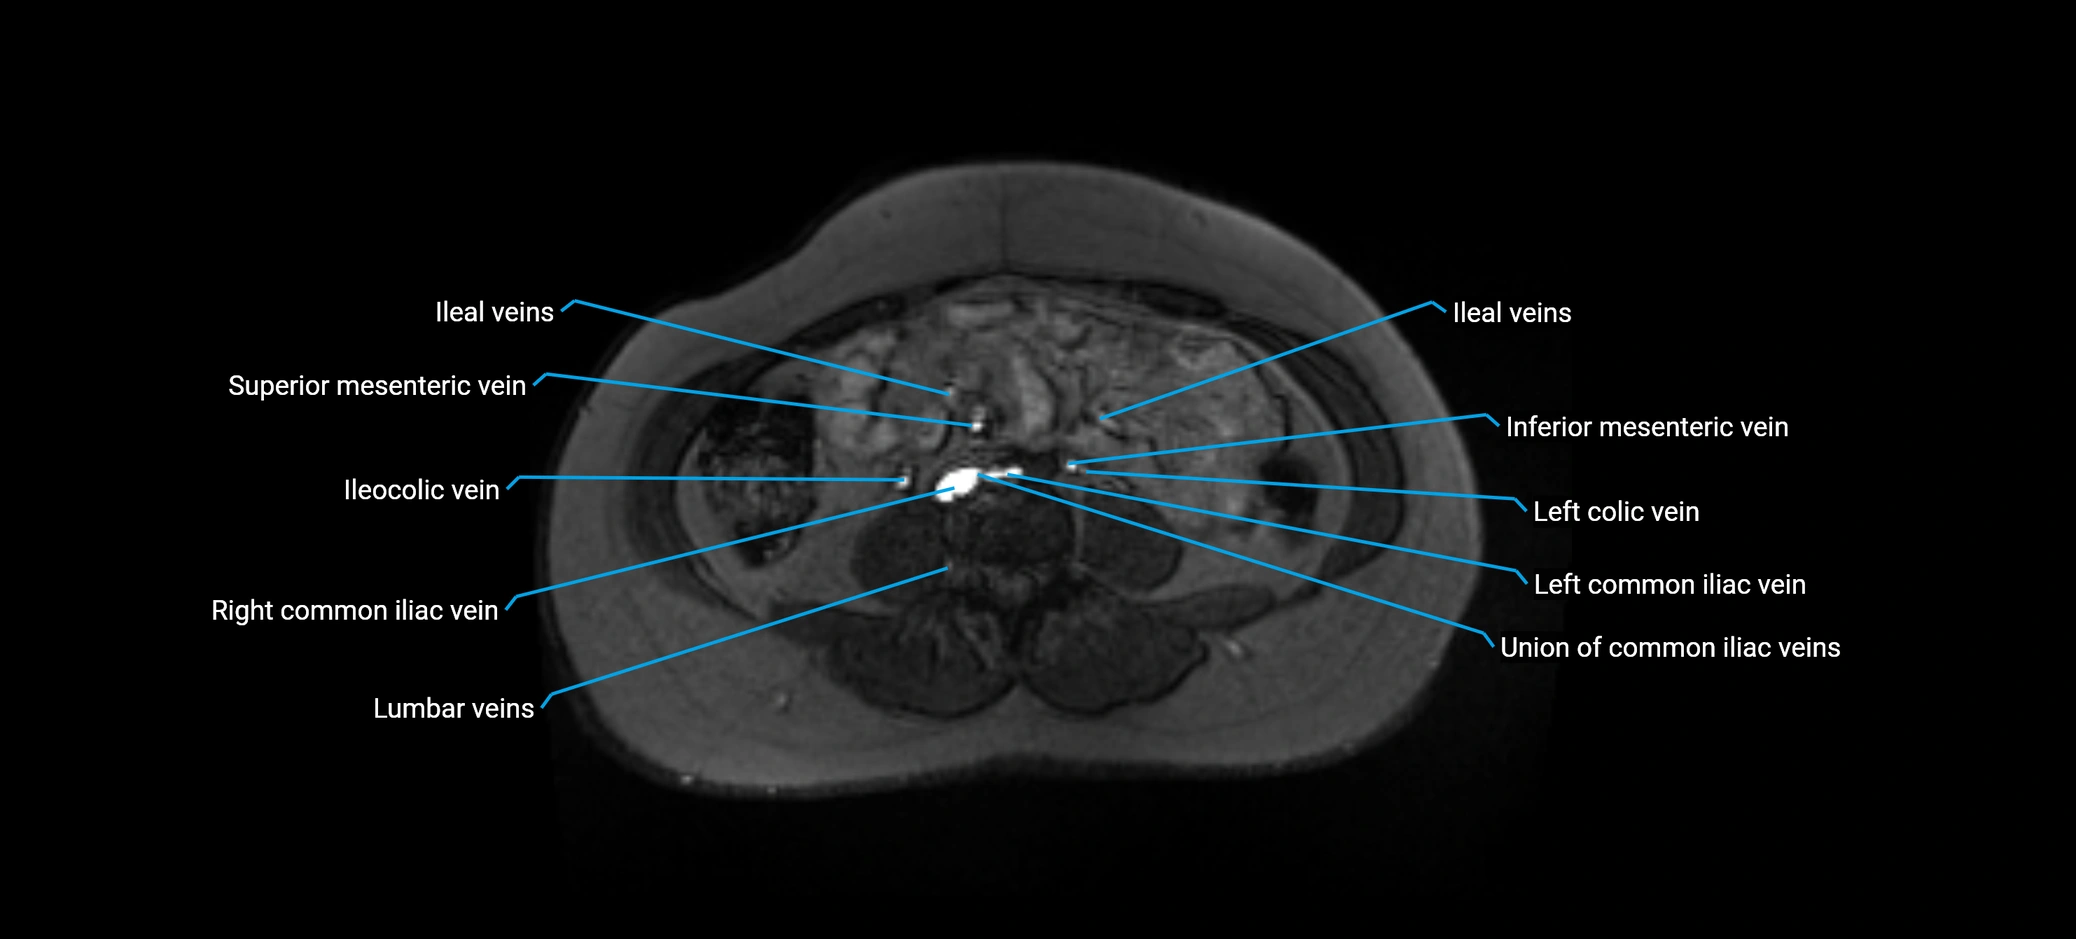

MRI image

image